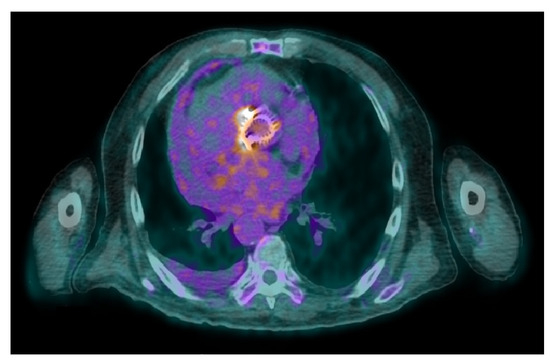

- Identifying infections within the heart: this includes detecting infections in native valves, prosthetic valves, and implanted cardiac devices. Performance varies depending on the location: sensitivity is low for native valve infections and for infections involving cardiac device leads. Sensitivity is significantly higher for prosthetic valve infections and infections within cardiac device pockets. Specificity remains high across all these scenarios;

- Uncovering hidden infectious spread: FDG-PET/CT can also detect clinically silent disseminated infectious disease, identifying primary infection source, and/or septic embolism, which can be crucial for diagnosis and guiding patient management.